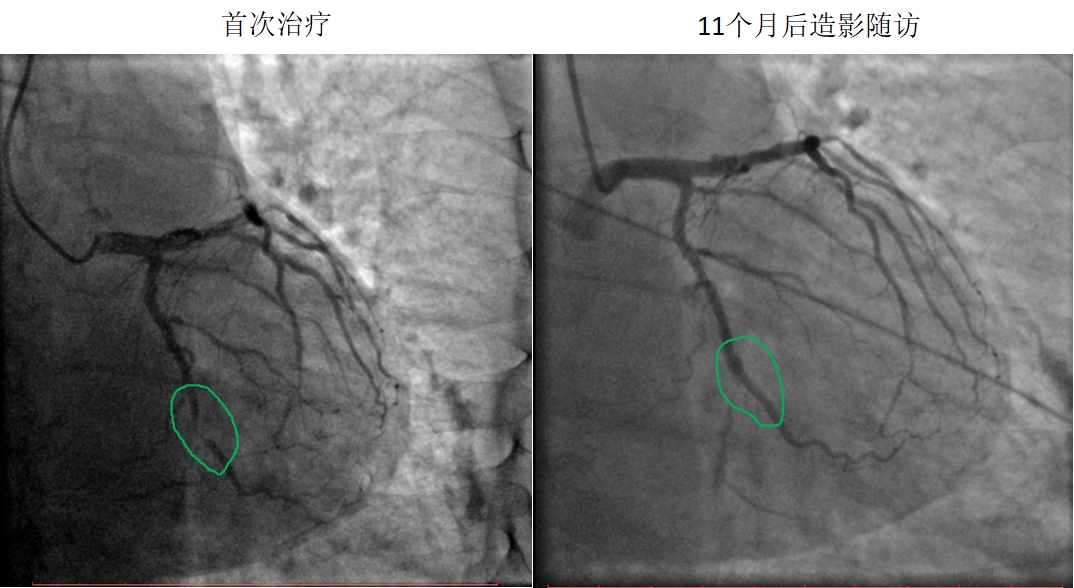

藥物球囊治療閉塞病變

患者:男,51歲

病變部位:LCX中段OM處100%閉塞

使用藥物球囊:2.0 x 20 mm

11個月后造影

隨訪:LCX中段OM發出處通暢